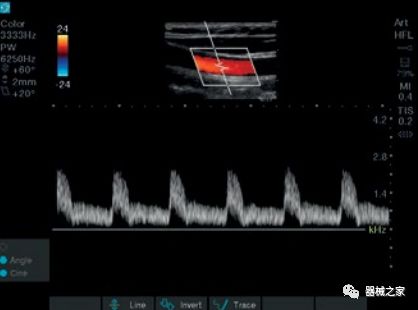

在几年前,超声波无法对小型慢流血管中的血流进行成像,但现在有少数供应商提供具有此功能的系统。该特征提供了另外一种检查病变以指示癌症或炎症的方法。其中一个是佳能Aplio 900 CV系统,它可以显示毛细血管中的血流量。日立的Arietta 65中程系统提供了一种可视化小血管的功能,可以更好地观察肾脏等器官的灌注情况。三星RS85还提供MV-Flow可视化慢流微血管结构。

佳能Aplio 900 CV系统还在2018年推出了一种新方法,通过称为四腔室跟踪的回声可视化心脏。它在一个三维视图中跟踪所有四个腔室的血容量。它提供腔室的舒张末期和收缩末期视图。这允许一次完成整个心脏功能的图像,而不是一次查看一个腔室。